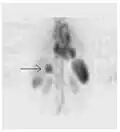

A nuclear medicine SPECT liver scan with technetium-99m labeled autologous red blood cells. A focus of high uptake (arrow) in the liver is consistent with a hemangioma. -